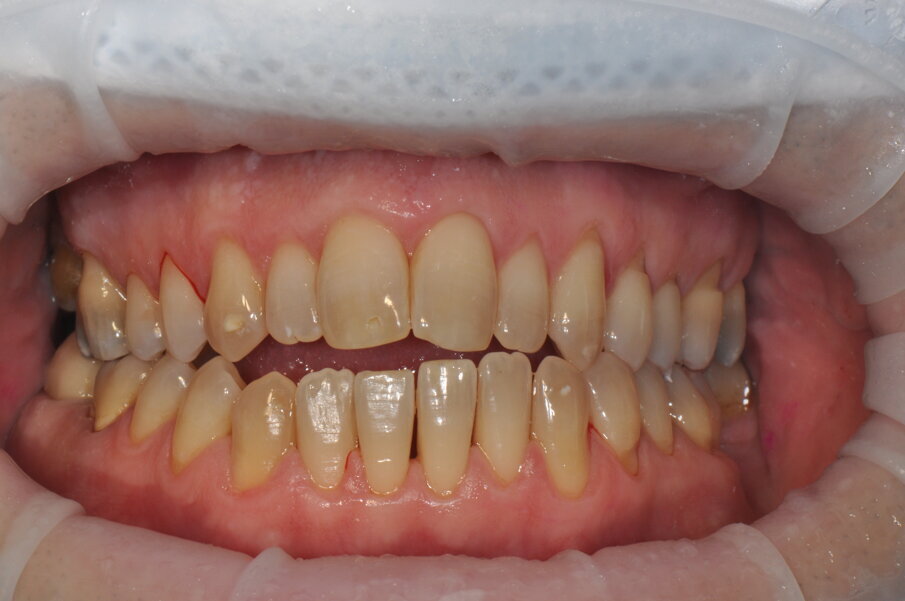

Fig. 6 - Fotografia frontale scattata prima della seduta di igiene orale professionale (Guided Biofilm Therapy).

Fig. 7 - Fotografia frontale scattata dopo la seduta di igiene professionale mediante l’utilizzo del sistema Airflow® Prophylaxis Master (EMS®) con polvere a base di eritritolo® e ablatore a ultrasuoni con punta perioslim (PS, EMS®).